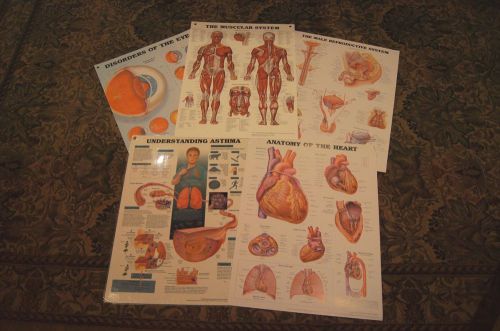

MEDICAL - Education Charts - Five: Muscle-Heart-Eye Disorder-Asthma- Male Repro

NEW POSTER Anatomy of HEART FAILURE Professional Wall Chart ROCHE LABORATORIES